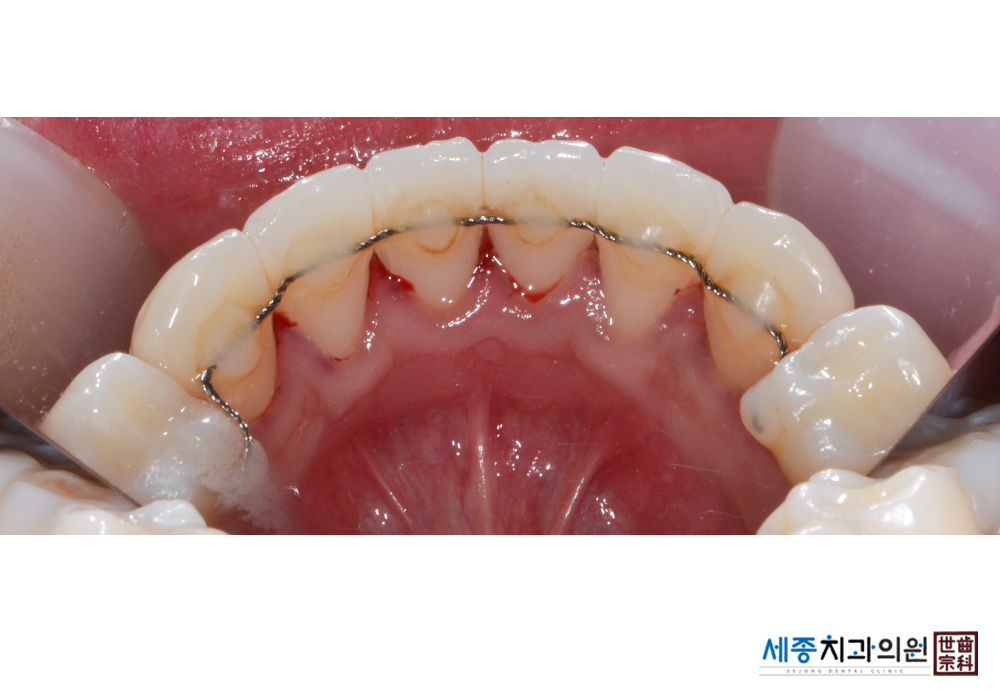

[스케일링] 치주질환 예방 스케일링 치료

치료전 : 2019-03-02

가글마취&저주파 스켈러를 사용한 스케일링